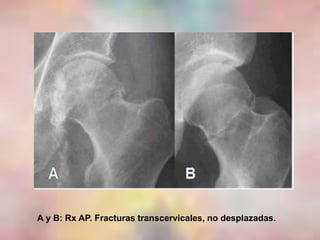

A y B: Rx AP. Fracturas transcervicales, no desplazadas.

A y B:Rx AP. Fracturas transcervicales, no desplazadas.